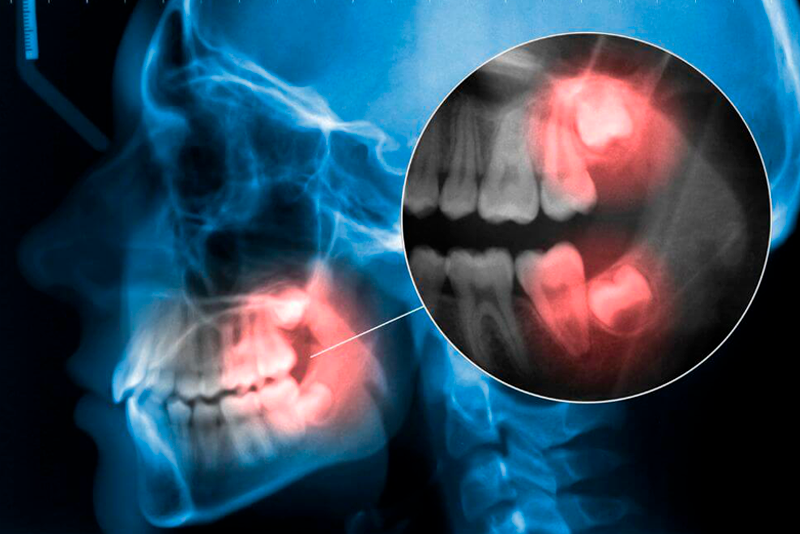

5.2. Chụp X-quang Răng

Chụp X-quang là một phương pháp cận lâm sàng không thể thiếu để chẩn đoán chính xác tình trạng răng khôn và các vấn đề liên quan. Có nhiều loại phim X-quang được sử dụng, phổ biến nhất là X-quang quanh chóp (nếu chỉ muốn kiểm tra một răng cụ thể) hoặc X-quang toàn cảnh (panoramic X-ray) để có cái nhìn tổng thể về cả hàm răng. Phim X-quang cung cấp thông tin quan trọng mà mắt thường không thể thấy được, bao gồm:

Hướng mọc của răng khôn: Xác định răng khôn đang mọc thẳng, mọc nghiêng (nghiêng gần, nghiêng xa, nghiêng má, nghiêng lưỡi), hay mọc ngang.

Vị trí và mức độ mọc ngầm: Cho biết răng khôn nằm hoàn toàn dưới xương, nằm dưới nướu, hay chỉ nhú lên một phần.

Mối quan hệ với các răng lân cận: Đánh giá mức độ ảnh hưởng của răng khôn đến răng số 7 kế cận, bao gồm nguy cơ tiêu chân răng số 7, sâu răng số 7 do kẹt thức ăn.

Tình trạng xương hàm: Phát hiện các dấu hiệu tiêu xương ổ răng, hoặc hình thành các ổ áp xe, u nang trong xương (nếu có).

Tương quan với các cấu trúc giải phẫu quan trọng: Đặc biệt là ống thần kinh dưới hàm và xoang hàm trên, giúp bác sĩ lập kế hoạch điều trị an toàn, đặc biệt là nếu cần nhổ răng khôn.